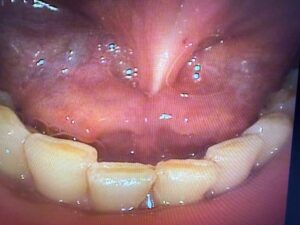

舌小帯短縮症の治療例

IMG_9747